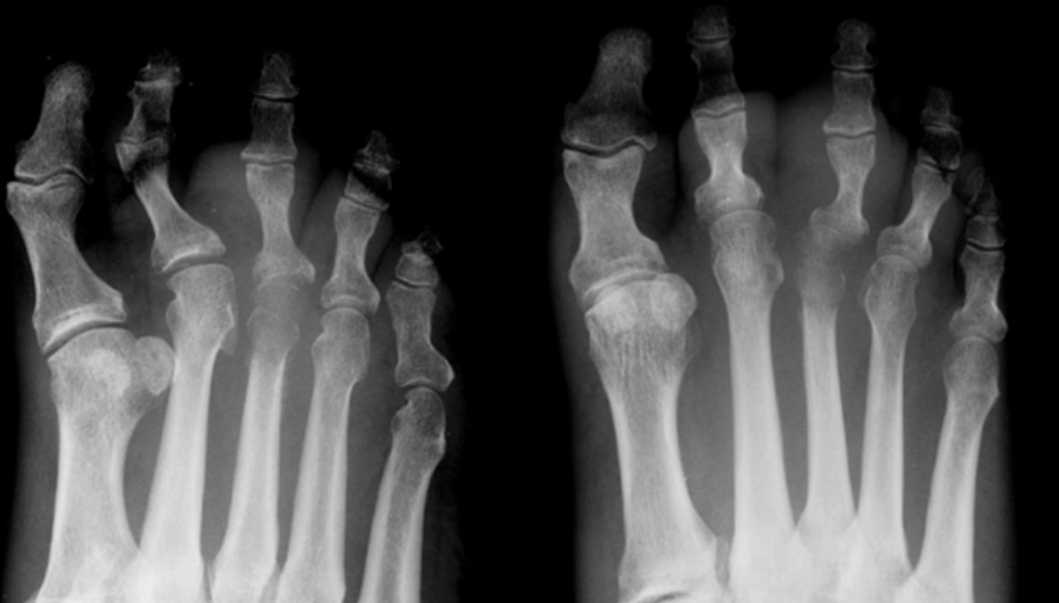

15

Q

Patient is radiographed 10 days after onset of forefoot pain.

Which structure is affected by avascular necrosis?

A

Third metatarsal head

Freiberg disease

16

Patient is radiographed 19 days after onset of forefoot pain.

What is the diagnosis?

What are two underlying conditions which may result in this specific diagnosis?

Diabetes, alcoholism

osteochondrosis (AVN) of metatarsal head (3rd)